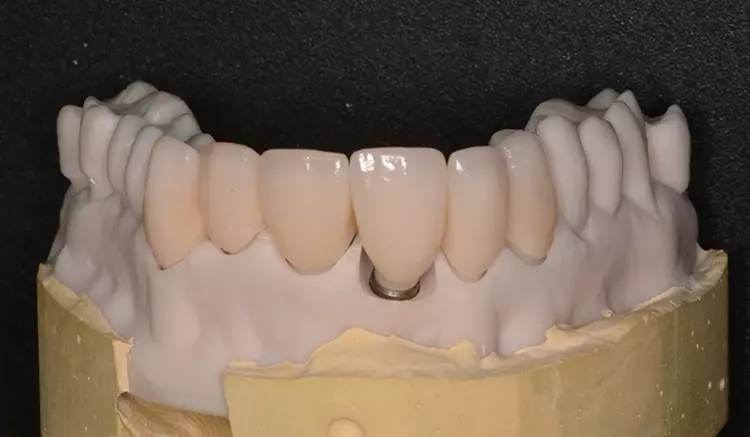

Neuversorgung Oberkieferfront auf Altimplantat 21

Die 49-jährige Patientin beklagte die ungleiche Höhe der Schneidekanten an den Kronen 11 und 21. In diesem Zusammenhang wurde das Gesamterscheinungsbild analysiert und entschieden, die Zähne 13-23 zu überkronen und dabei die Altkronen an 11 und an dem Implantat 21 zu erneuern. Die verschachtelt stehenden Zähne im Unterkiefer sollen im Nachgang per Aligner-Therapie ausgerichtet werden.

Dabei wurde die beabsichtigte Situation im Vorab per Wax-up simuliert. Beim Entfernen der Altkrone 21 wurde ersichtlich, dass ein Titanabutment eingesetzt wurde, an dem sich Konkremente und Zementreste befanden, die zu einer marginalen Mukositis am Implantat führten.